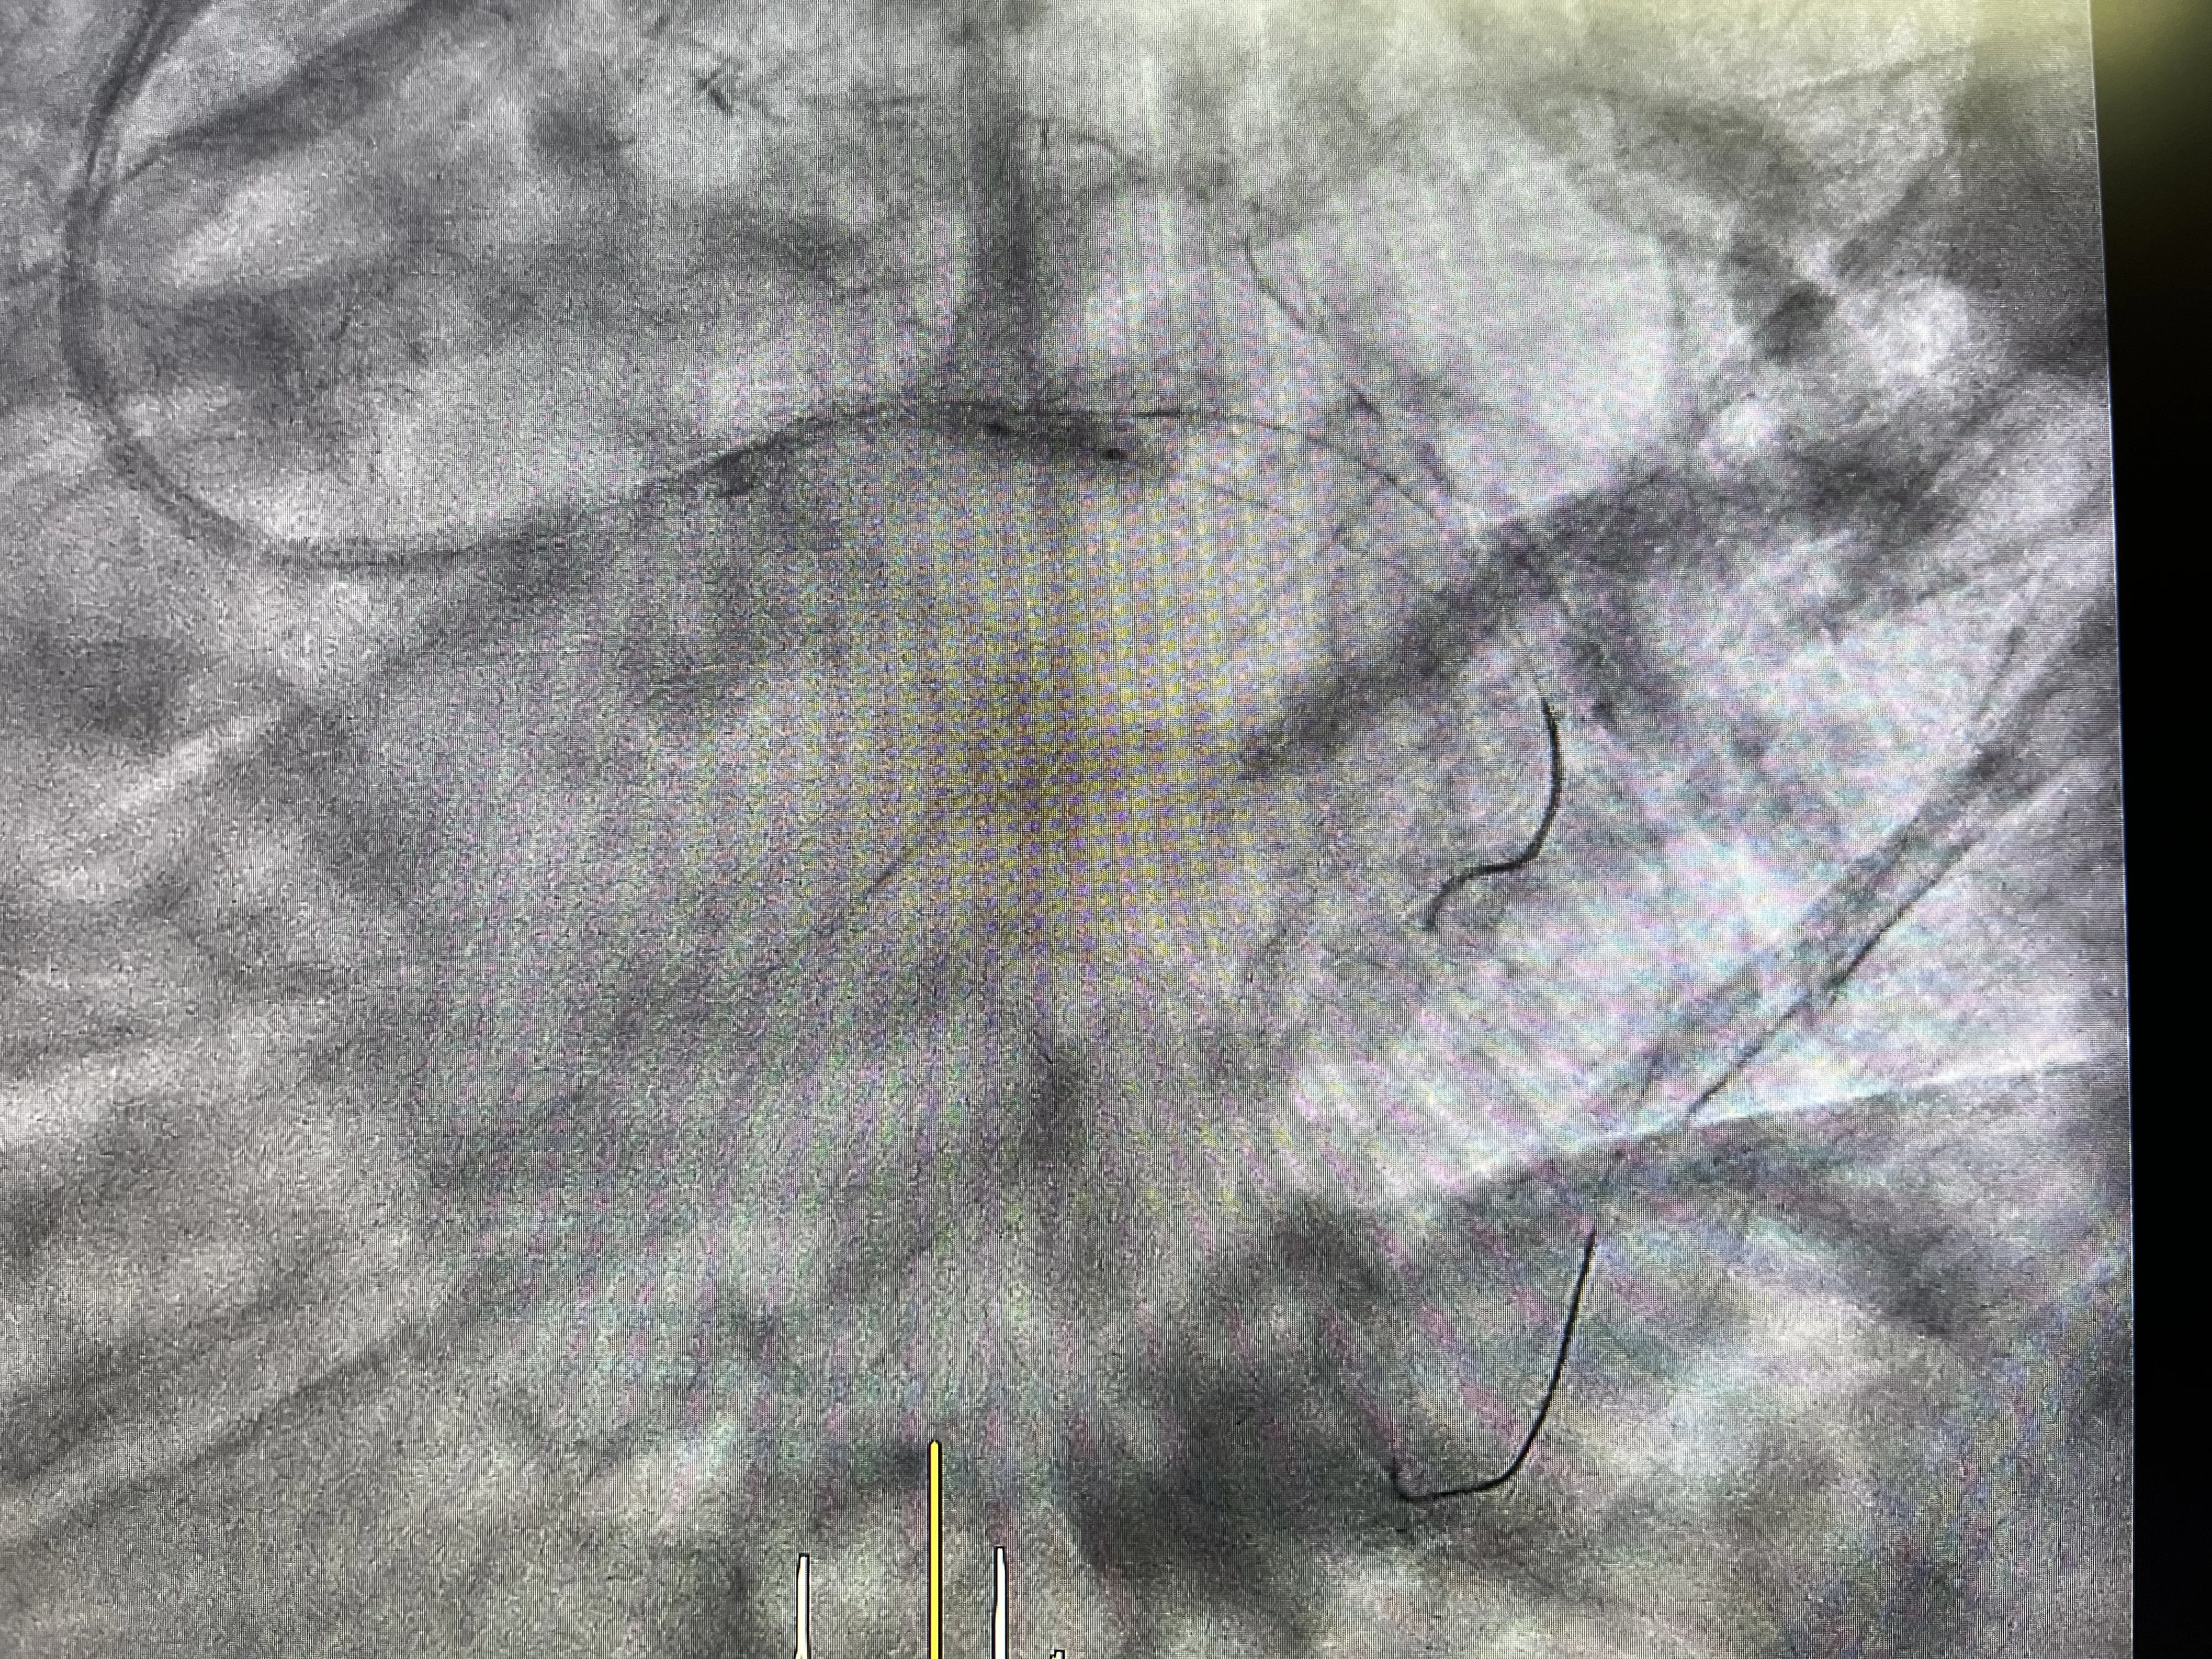

Evaluación del bypass en la angiografía

La angiografía realizada durante el cateterismo reveló que el bypass está en buen estado y cumple su función de irrigar la arteria descendente anterior. Este hallazgo es positivo, ya que indica que el bypass sigue siendo una vía efectiva para mantener el flujo sanguíneo al corazón, a pesar de las obstrucciones presentes en las arterias coronarias nativas.

Uso del balonfármaco en el ostium de la circunfleja

Para tratar la estrechez en el ostium de la arteria circunfleja, se utilizó un balonfármaco. Este dispositivo combina la dilatación mecánica de la arteria con la liberación de medicamentos que ayudan a prevenir la reestenosis. La aplicación del balonfármaco en el ostium es una estrategia eficaz para mejorar el flujo sanguíneo y reducir el riesgo de futuras obstrucciones en esta área crítica.

Resultado angiográfico tras el tratamiento

El resultado angiográfico posterior al tratamiento con el balonfármaco mostró una mejora significativa en el flujo sanguíneo a través de la arteria circunfleja. La intervención percutánea logró abrir el ostium, permitiendo un paso más libre de sangre y aliviando los síntomas de angina del paciente. Este resultado es alentador y demuestra la eficacia del tratamiento percutáneo en el manejo de obstrucciones coronarias.